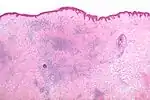

Микроскопия

Гистоморфологические появления укусов насекомых, как правило, характеризуются появлением сосудистого инфильтрата, состоящего из лимфоцитов и эозинофилов.